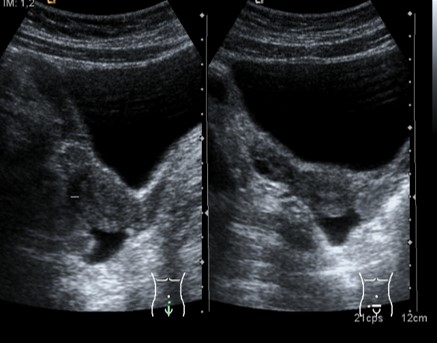

Aprovechando la vejiga repleccionada hacemos cortes axiales (rojo) y longitudinales (amarillo). No me atrevo ni a poner unas pautas de búsqueda como en la Próstata.

Transverso.

Longitudinal.